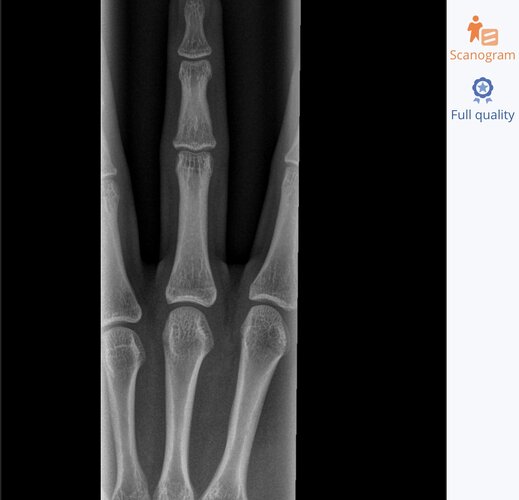

Based off this x ray that I got around a year and a half ago do you guys think I am still growing? I’m 5’11 and I’ve noticed that I haven’t grown in a while so I want to know if I’m done growing. Is 6’3 possible?

The photo seems to have gotten squished. Hopefully this is better

closed. you can ask the doctor who took these xrays. Mine told me my plates were shut without me even asking a few weeks ago